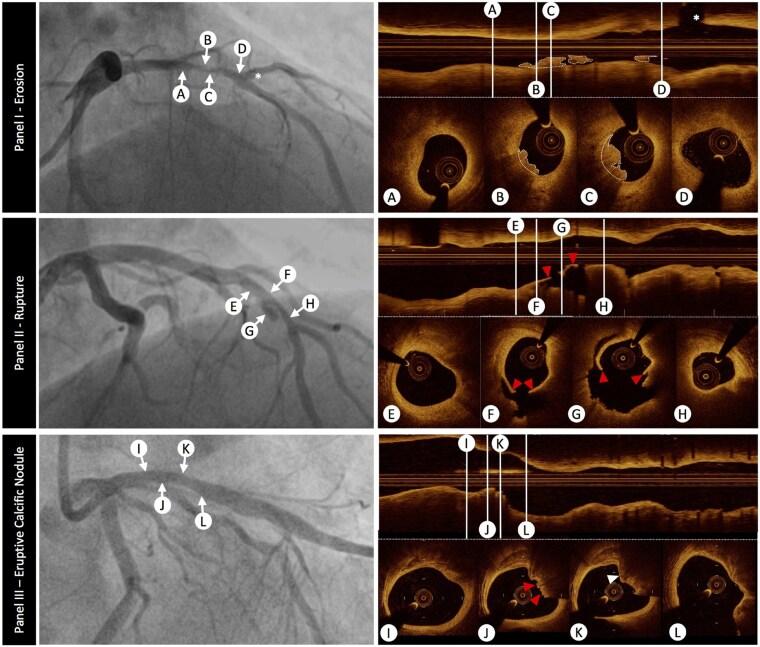

Despite advances in research and patient management, atherosclerosis and its dreaded acute and chronic sequelae continue to account for one out of three deaths globally. The vast majority of acute coronary syndromes (ACS) arise from either plaque rupture or erosion, but other mechanisms, including calcific nodules, embolism, spontaneous coronary artery dissection, coronary spasm, and microvascular dysfunction, can also cause ACS. This ACS heterogeneity necessitates a paradigm shift in its management that extends beyond the binary interpretation of electrocardiographic and biomarker data. Indeed, given the evolution in the global risk factor profile, the increasing importance of previously underappreciated mechanisms, the evolving appreciation of sex-specific disease characteristics, and the advent of rapidly evolving technologies, a precision medicine approach is warranted. This review provides an update of the mechanisms of ACS, delineates the role of previously underappreciated contributors, discusses sex-specific differences, and explores novel tools for contemporary and personalized management of patients with ACS. Beyond mechanistic insights, it examines evolving imaging techniques, biomarkers, and regression- and machine learning-based approaches for the diagnosis (e.g. CoDE-ACS, MI3) and prognosis (e.g. PRAISE, GRACE, SEX-SHOCK scores) of ACS, along with their implications for future ACS management. A more individualized approach to patients with ACS is advocated, emphasizing the need for innovative studies on emerging technologies, including artificial intelligence, which may collectively facilitate clinical decision-making within a more mechanistic framework, thereby personalizing patient care and potentially improving long-term outcomes.

尽管在研究和患者管理方面取得了进展,但动脉粥样硬化及其可怕的急慢性后果仍然是全球三分之一死亡的原因。绝大多数急性冠状动脉综合征(ACS)源于斑块破裂或糜烂,但其他机制,包括钙化结节、栓塞、自发性冠状动脉夹层、冠状动脉痉挛和微血管功能障碍,也可导致ACS。这种ACS的异质性使得其管理模式需要发生转变,这种转变不仅仅局限于对心电图和生物标志物数据的二元解读。事实上,鉴于全球风险因素状况的演变、先前未被充分认识的机制的重要性日益增加、对性别特异性疾病特征的认识不断发展以及快速发展的技术的出现,精准医学方法是必要的。本综述提供了ACS机制的最新情况,阐述了先前未被充分认识的因素的作用,讨论了性别差异,并探索了用于当代和个性化管理ACS患者的新工具。除了机制方面的见解,它还研究了用于ACS诊断(如CoDE-ACS、MI3)和预后(如PRAISE、GRACE、SEX-SHOCK评分)的不断发展的成像技术、生物标志物以及基于回归和机器学习的方法,以及它们对未来ACS管理的影响。提倡对ACS患者采取更个体化的方法,强调需要对包括人工智能在内的新兴技术进行创新性研究,这些技术可能共同促进在更具机制性的框架内进行临床决策,从而实现患者护理的个性化并可能改善长期预后。